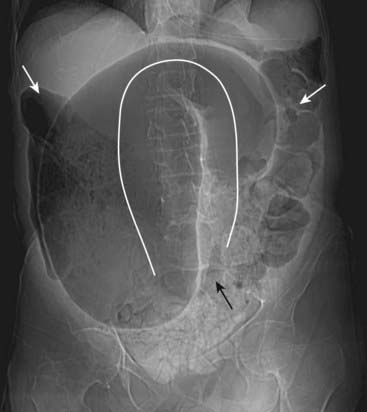

Figure 14-1 Sentinel loops from pancreatitis.

A single, persistently dilated loop of small bowel is seen in the left upper quadrant (solid white arrows) on both the supine (A) and prone (B) radiographs of the abdomen. A sentinel loop or localized ileus often signals the presence of an adjacent irritative or inflammatory process. This patient had acute pancreatitis.